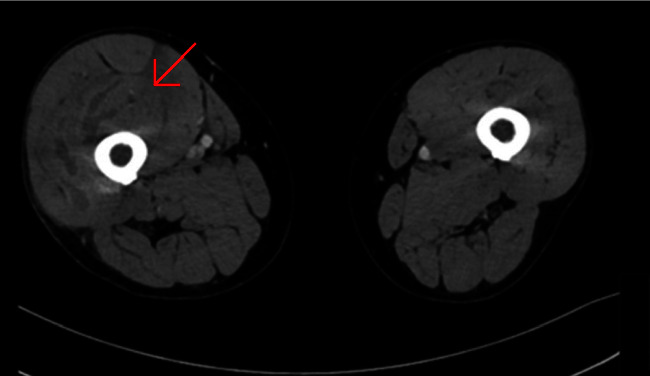

Pyomyositis, accompanied by aseptic arthritis, has been previously documented in several publications. However, none of the authors in the mentioned case reports offered a pathophysiological explanation for this unusual phenomenon or proposed a treatment protocol. We present a case of a healthy, 70-year-old male who was presented to the emergency department 4 days after tripping over a pile of wooden planks and getting stabbed by a nail to his thigh. The right thigh was swollen. Unproportional pain was produced by a light touch to the thigh. A laboratory test and a CT scan were obtained. The working diagnosis was pyomyositis of the thigh and septic arthritis of the ipsilateral knee. The patient underwent urgent debridement and irrigation of his right thigh. An arthroscopic knee lavage was performed as well. Intraoperative cultures from the thigh revealed the growth of Streptococcus pyogenes and Staphylococcus aureus. Cultures from synovial fluid were sterile; thus, septic arthritis was very unlikely. The source of the knee effusion might have been an aseptic inflammatory response due to the proximity of the thigh infection. Anatomically, the quadriceps muscle inserts on the patella, and its tendon fuses with the knee capsule, creating a direct fascial track from the thigh to the knee. The inflammatory response surrounding the infection may have followed this track, creating a domino effect, affecting adjacent capillaries within the joint capsule, and causing plasma leakage into the synovial space, leading to joint effusion. Our suggested treatment is addressing the primary infection with antibiotics and considering adding anti-inflammatory therapy, given our suspicion that this process has an inflammatory component.

Abstract Image